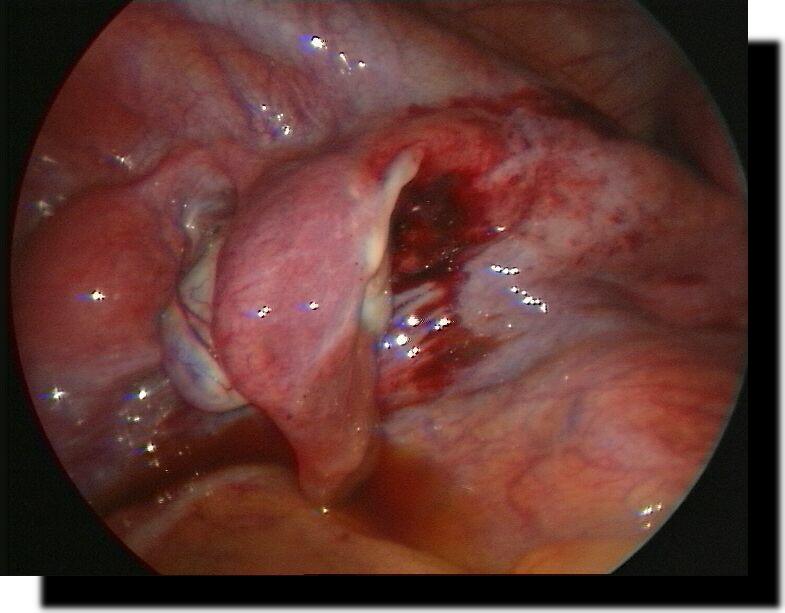

große Hiatushernie + upside-down-stomach

Magenperforation

Z.n. laparoskopischer Ulcusbiopsie und Magenperforations-Übernähung

grosse Hiatushernie

+ upside-down-stomach

Magenkarzinom